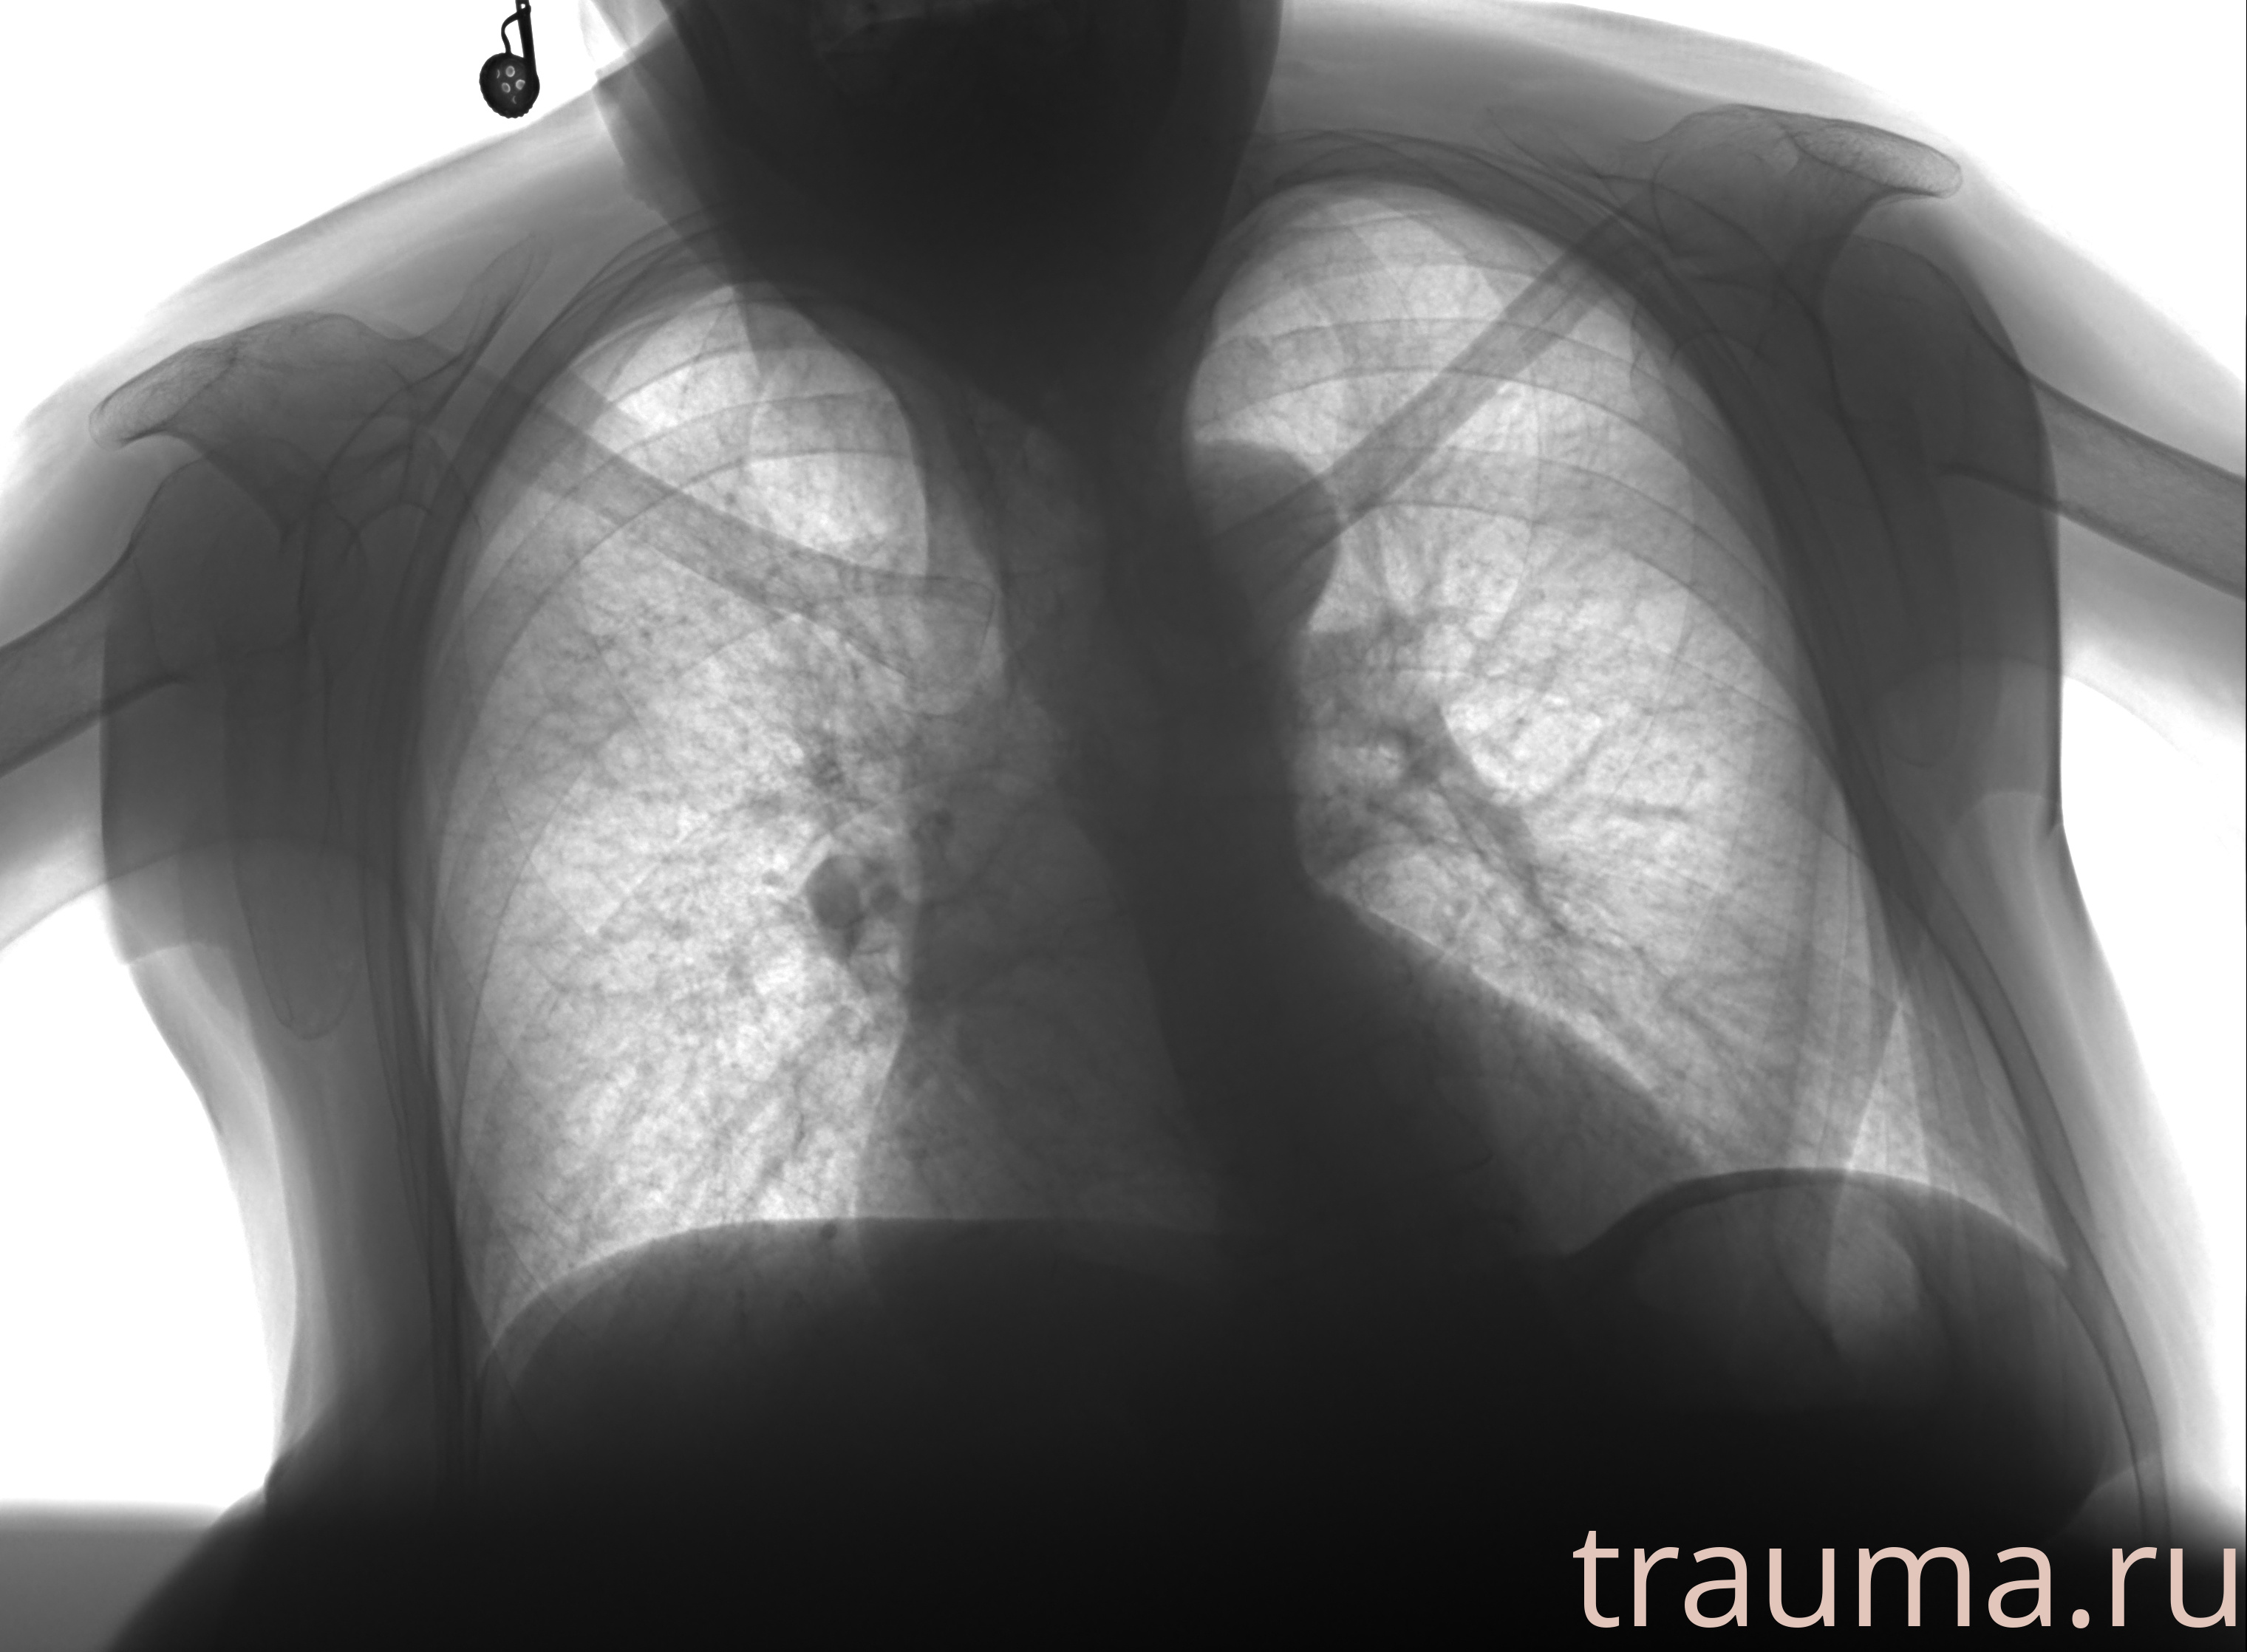

Рентгенограммы

Рентген на дому: по вашему адресу приезжает врач-рентгенолог, травматолог-ортопед с мобильным рентгеновским аппаратом, проводит диагностику травмы или заболевания, делает необходимые рентгенограммы, дает рекомендации по дальнейшему лечению. Получить качественные снимки в домашних условиях возможно благодаря уникальной методике, разработанной МосРентген Центром для института  Склифосовского

при переломе шейки бедра и пневмонии от компании МосРентген Центр - партнера Института имени Склифосовского